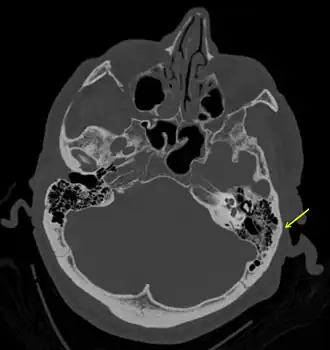

| Uma fratura sutil do osso temporal vista na TC de uma pessoa com traumatismo craniano grave | |

Este tipo de fratura normalmente exige um grau significativo de trauma para ocorrer.[1] A fratura é de pelo menos um dos seguintes ossos: osso temporal, osso occipital, osso esfenoide, osso frontal ou osso etmoide.[1] Eles são divididos em fraturas da fossa anterior, fossa média e fossa posterior.[1] Fraturas faciais também ocorrem frequentemente.[1] O diagnóstico geralmente é feito por tomografia computadorizada.[1]